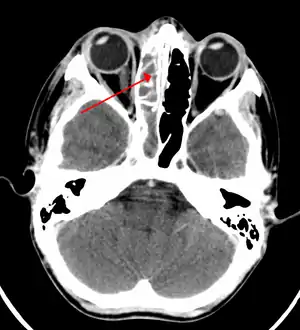

![]() | |

| A CT scan showing sinusitis of the ethmoid sinus | |

CT of chronic sinusitis

CT scan of chronic sinusitis, showing a filled right maxillary sinus with sclerotic thickened bone.

Maxillary sinusitis caused by a dental infection associated with periorbital cellulitis